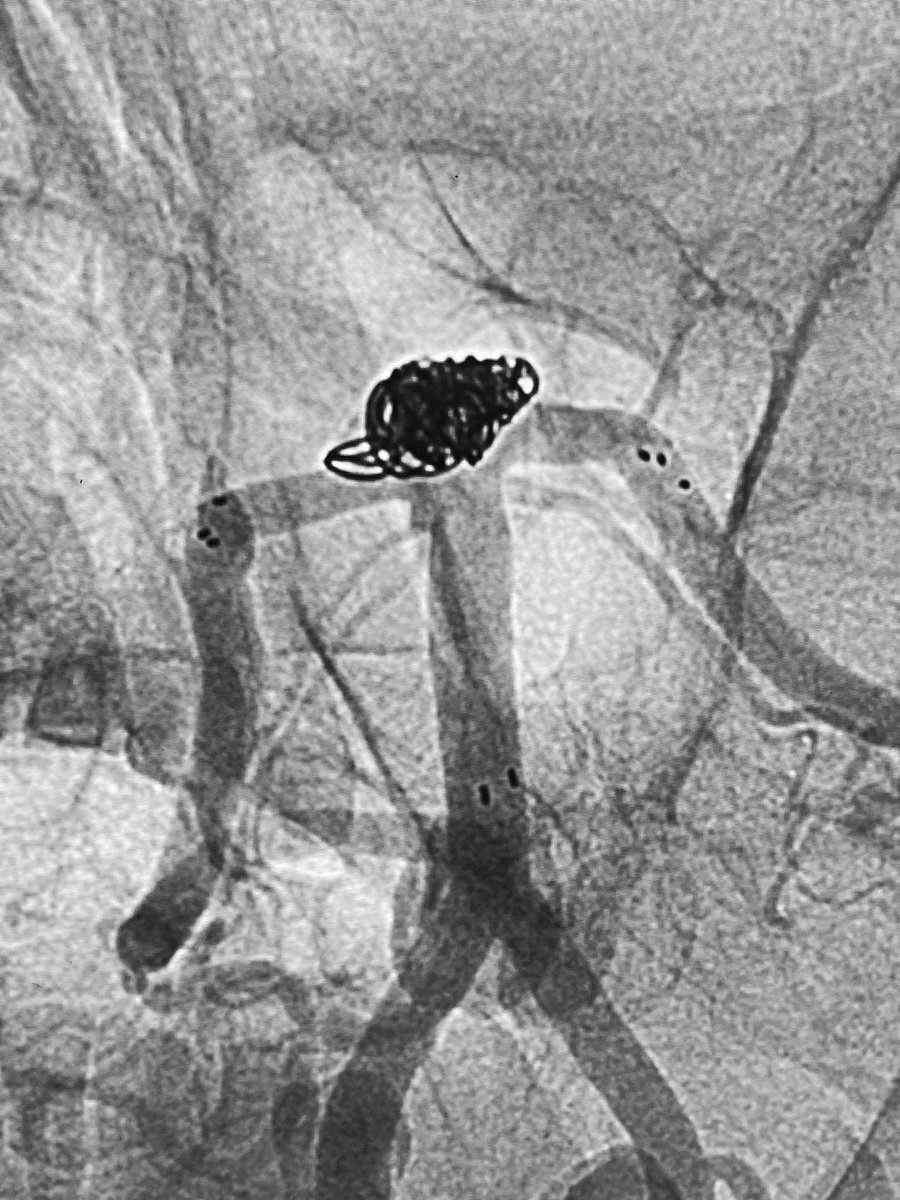

Type D2 CCF, closed by ipsilateral transvenous double-catheter technique for coiling and onyx injection. Minimal approach for better results :))